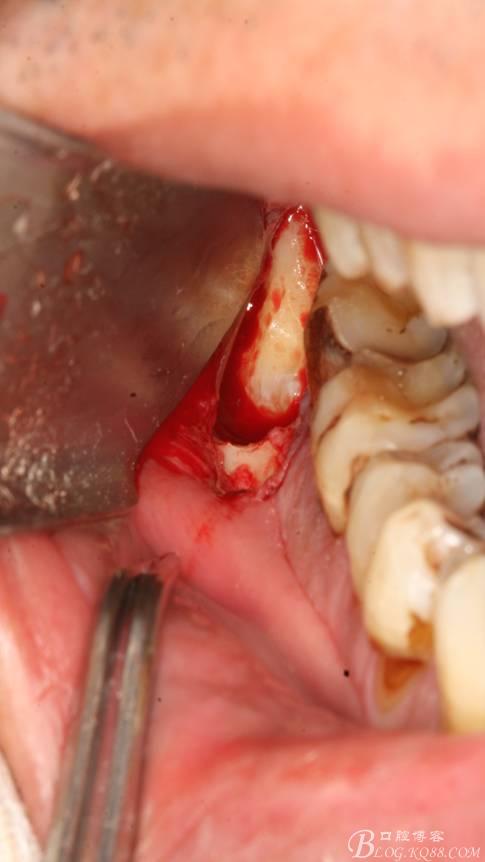

2.切開(kāi)翻瓣

3.去骨、暴露48.

4. 縱分牙根和牙冠